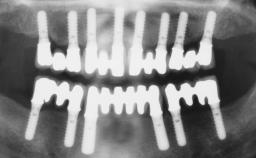

A 56-year-old female patient was referred to the clinic because of retention problems with her mandibular denture. She had been completely edentulous for more than 33 years and wore her sixth set of complete conventional dentures, which had been delivered 5 years previously. An oral surgeon had performed a vestibuloplasty in the interforaminal region of the mandible with a piece of skin tissue 12 years earlier. The panoramic radiograph and lateral cephalometric radiograph exhibited the hypotrophy of the inferior alveolar process. The mandible was a Cawood class VI,and the height of the mandible in the interforaminal zone was 15 mm.

Defining Characteristics Fully edentulous lower jaw to be rehabilitated with two or more implants

Modality 2 interforaminal implants

Bone Volume Horizontally and vertically sufficient